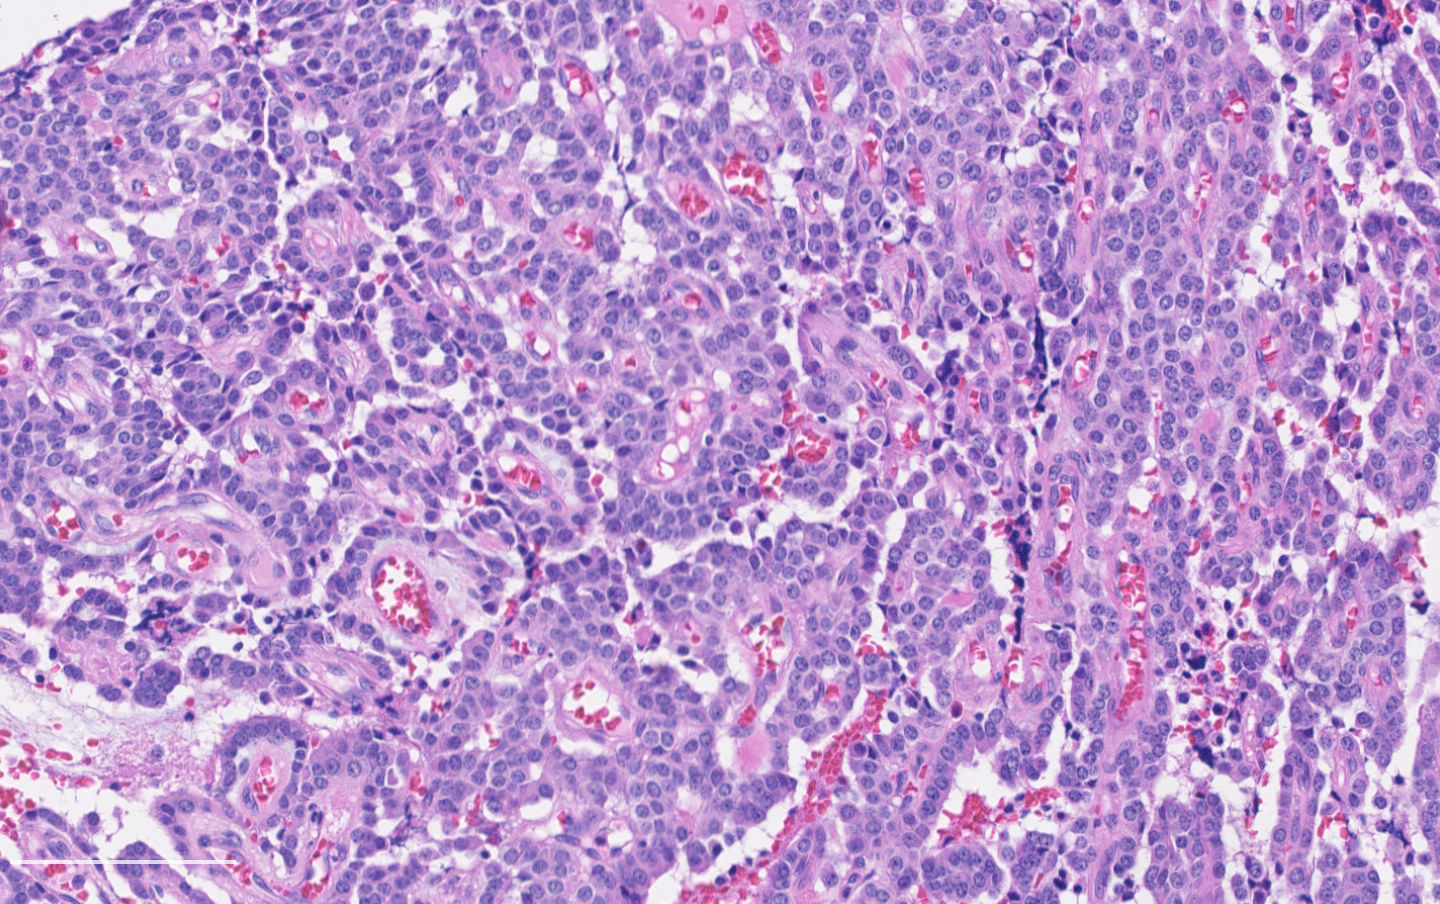

- Diagnostic criteria:

- Neuroendocrine morphology with 2 - 10 mitoses per 2 mm² or presence of necrosis

- Necrosis can be in large zones but is usually punctate

- Mitotic rate should be counted in the area with the highest proliferation rate (hot spot)

- Neuroendocrine histologic patterns similar to typical carcinoids: organoid, trabecular, rosette formation, papillary, pseudoglandular, follicular

- Tumor cells are as typical carcinoid: uniform with a polygonal shape, round to oval nuclei with salt and pepper chromatin and inconspicuous nucleoli, along with moderate to abundant eosinophilic cytoplasm

- Greater pleomorphism than for typical carcinoid is common (Arch Pathol Lab Med 2010;134:1628)

- Stroma is fine and highly vascularized; hyalinization, cartilage or bone formation are possible

Contributed by Philippe Joubert, M.D., Ph.D.